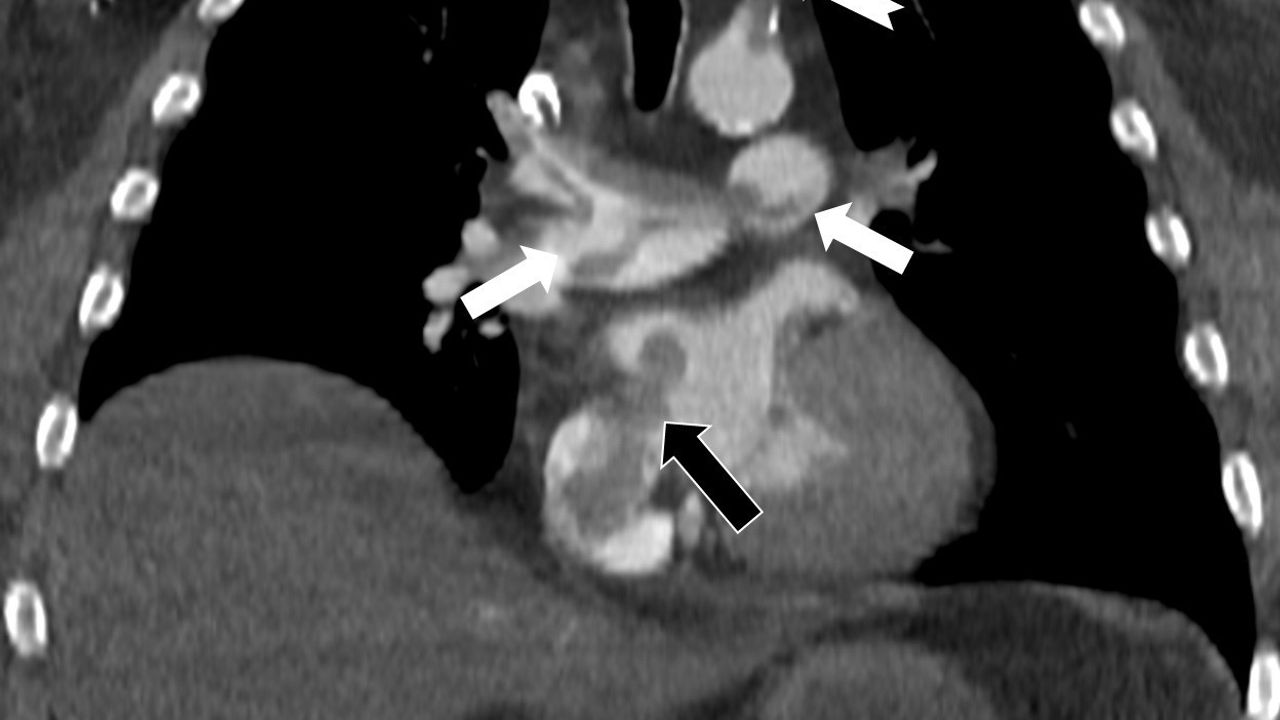

Bir dönem Özel Denizli Tekden Hastanesi'nde de görev yapan Prof. Dr. Nevzat Karabulut'un yaptığı çalışmada; akciğerin bilgisayarlı tomografi anjiyografisi sayesinde toplar damarlardan kaynaklanan pıhtının akciğer damarlarını tıkaması yanında, kalpteki delik nedeniyle kalbin sağ tarafından sol tarafına geçerek ana atardamara ulaştığı ve sol kol damarını tıkadığı gösterildi.

Emboli görüntülemesi konusunda çok sayıda bilimsel çalışması bulunan Prof. Dr. Karabulut, genelde bacak damarlarından kaynaklanan pıhtıların ölümcül olabilen akciğer embolisine yol açması yanında, kalp deliği olan hastalarda ana atardamar yoluyla beyin, kol ve bacak gibi vücudun diğer bölgelerine de geçerek ani damar tıkanmasına (paradoks emboli) bağlı bulgulara yol açtığını belirtti. Prof. Dr. Karabulut'un çalışmasında nedeni bilinmeyen pıhtı atmalarında kalpteki gizli deliklerin mutlaka araştırılması gerektiği vurgulanarak ekokardiyografi ve bilgisayarlı tomografi tetkiklerinin erken ve doğru tanı koymada hayat kurtarıcı rolüne dikkat çekildi.